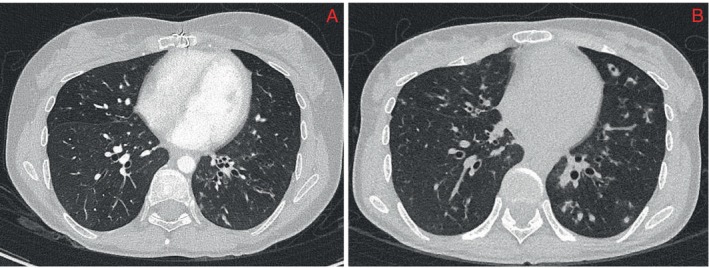

在处理重症肌无力患者的脓肿分枝杆菌肺病方面的指导有限。大环内酯类药物和氨基糖苷类药物是治疗脓肿支原体肺病的主要药物,但由于有诱发重症肌无力的危险,因此在重症肌无力患者中避免使用。29岁女性,有抗乙酰胆碱受体抗体阳性重症肌无力和支气管扩张病史,诊断为脓肿支原体肺病。患者开始安全使用大环内酯为基础的方案并密切监测,静脉注射免疫球蛋白(1 g/kg)、强的松龙10 mg、利妥昔单抗500 mg进行预处理,并使用吡哆斯的明和3,4-二氨基吡啶增强神经肌肉接点。她在家庭项目中安全出院,并取得了临床、放射学和微生物学反应。

There is limited guidance on managing Mycobacterium abscessus pulmonary disease in Myasthenia Gravis patients. Macrolides and aminoglycosides form the backbone of M. abscessus pulmonary disease treatment but are avoided in Myasthenia Gravis patients due to the risk of precipitating myasthenic crisis. A 29-year-old female, with a history of anti-acetylcholine receptor antibody-positive Myasthenia Gravis and bronchiectasis, was diagnosed with M. abscessus pulmonary disease. She was commenced on a macrolide-based regime safely with close monitoring, pretreatment with intravenous immunoglobulin (1 g/kg),10 mg prednisolone, 500 mg rituximab and augmentation of the neuromuscular junction with pyridostigmine and 3,4-Diaminopyridine. She was safely discharged to the hospital in the home program and achieved clinical, radiological and microbiological response.